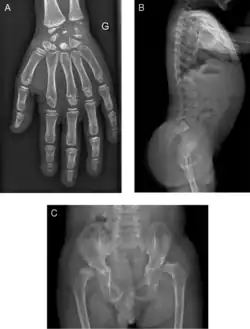

Radiograph of a WRS child presenting with dysplastic bone growth in various regions of the body.

Initially, patients with neonatal or early-childhood onset diabetes are possible candidates for having Wolcott–Rallison syndrome.[1] The other features include multiple epiphyseal dysplasia, osteopenia, intellectual disability, and hepatic and renal dysfunction.[1] Patients having features that suggest Wolcott–Rallison syndrome can be referred for genetics testing. The key way to test for this disease is through genetic testing for EIKF2AK3 mutations.[7] Molecular genetic analysis can be done for the patient and the parents to test for inherited or de novo mutations. It can also show whether the patient's parents are heterozygotes or homozygotes for the normal genotype.[4] X-rays can show bone age in relation to actual age. In typical WRS patients the bone age is a few years less than the chronological age.[4][5][8][9] Hypothyroidism is rare in WRS patients but can occur.[4]